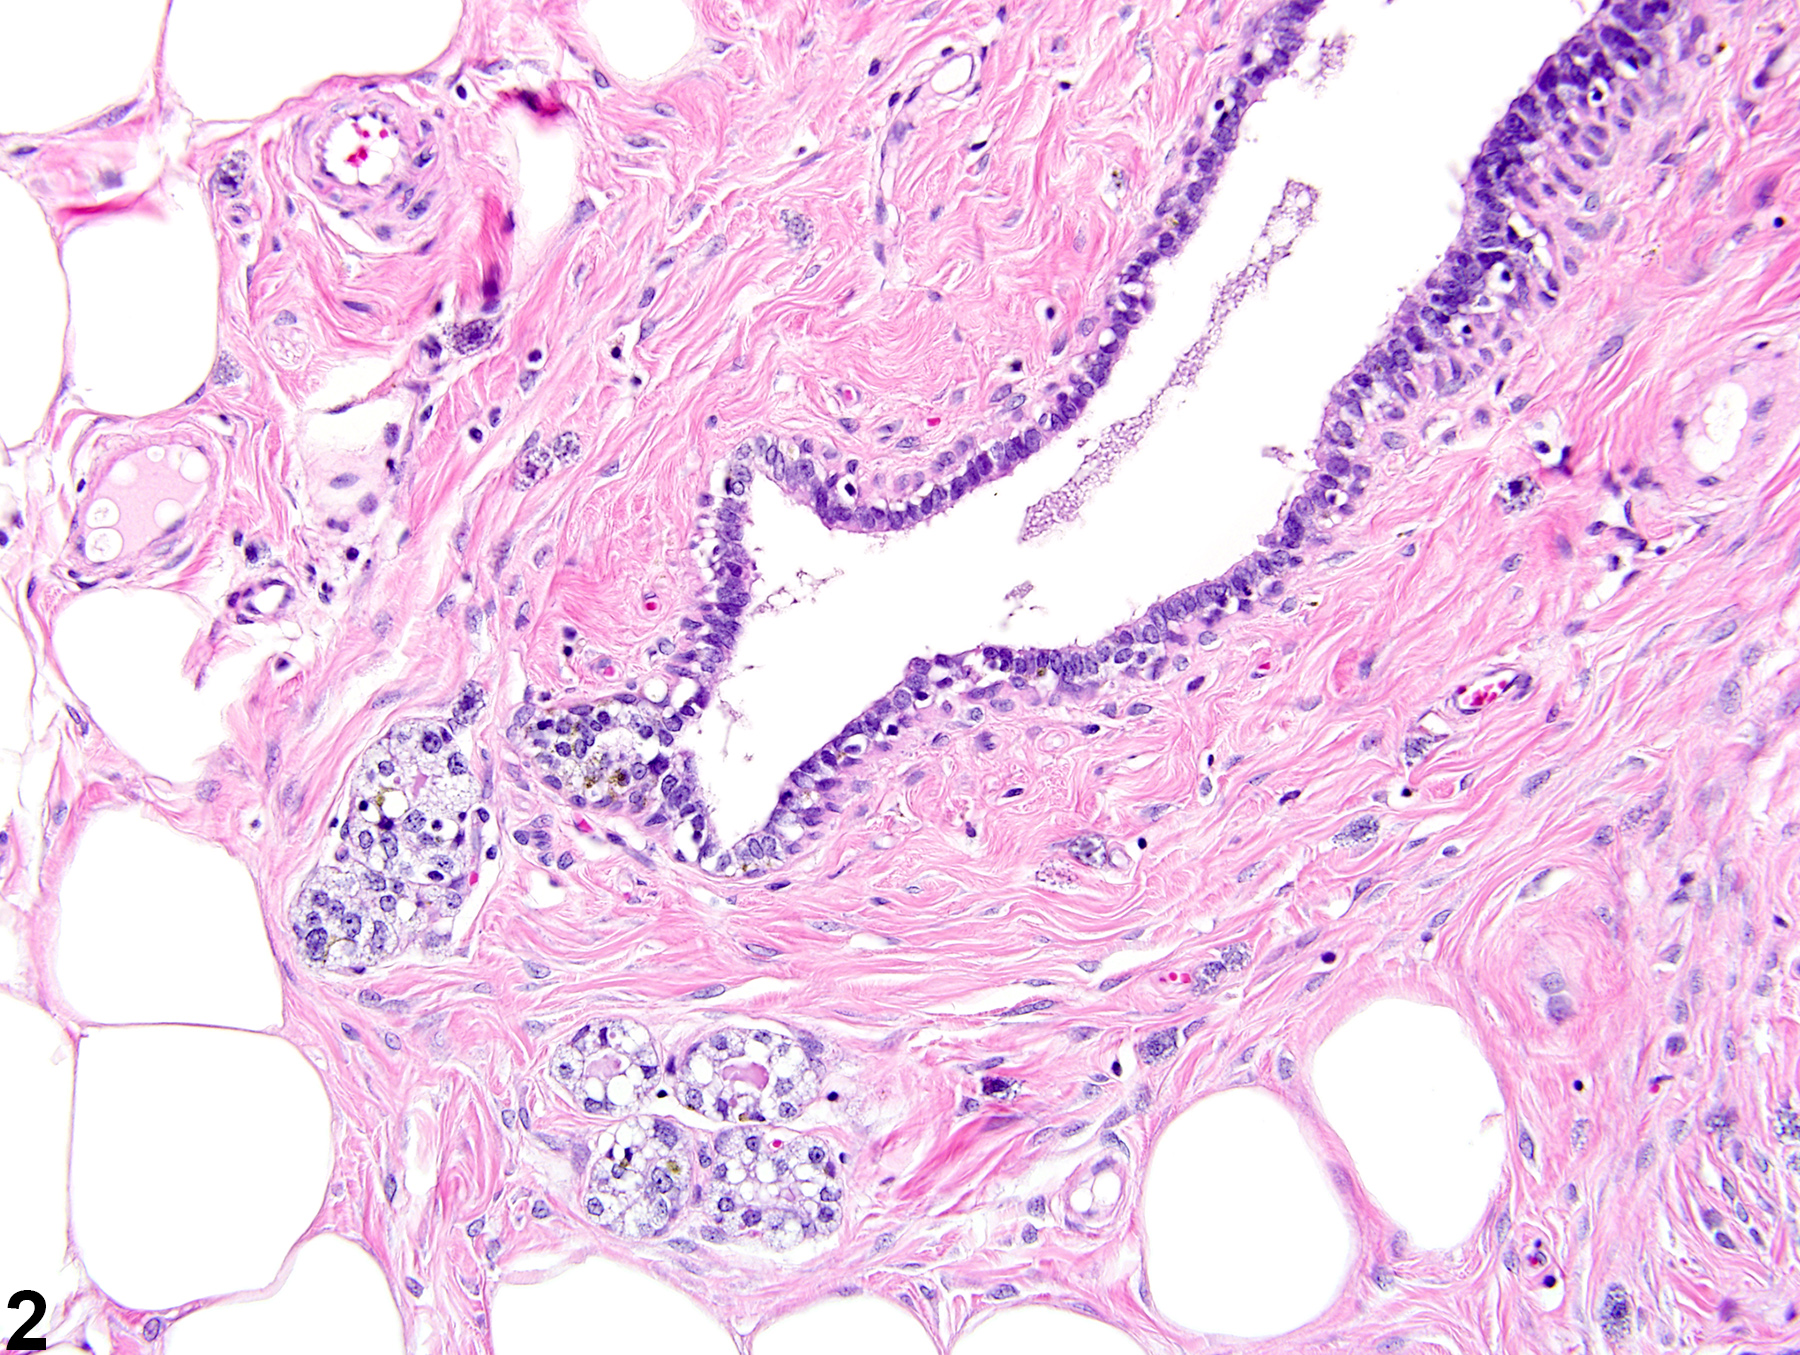

Mammary gland - Fibrosis in a male F344/N rat from a chronic study (higher magnification of Figure 1). Mature fibrous connective tissue surrounds a mammary gland duct and alveoli and extends into the adjacent mammary adipose tissue.